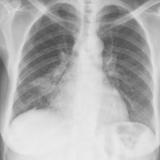

Case 1 PA

Date: 02/28/2004

Views: 3453